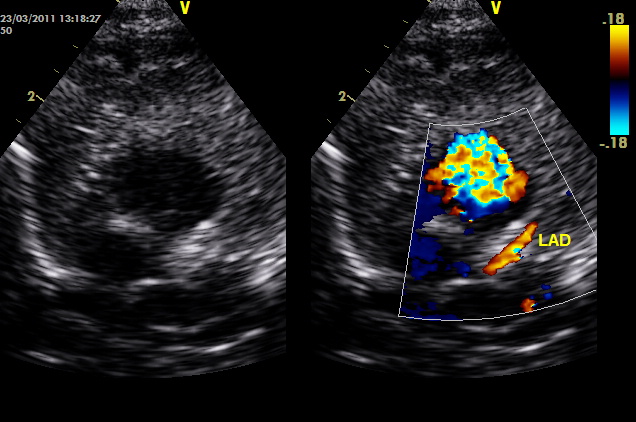

Υπερηχογράφημα (ECHO): φυσιολογική βασική ανατομία, φυσιολογικές διαστάσεις και λειτουργικότητα (συστολική και διαστολική λειτουργία, ελέγχθησαν και με ιστικό Doppler πέραν του συνήθους ελέγχου). Παρακάτω απεικονίζονται τα στεφανιαία. Ελέγχθηκε η έκφυση όχι μόνο με 2D, αλλά και με απεικόνιση της στεφανιαίας ροής με color Doppler (ασυνήθης πρακτική για παιδιά, θα εξηγηθεί ο λόγος στη συνέχεια).